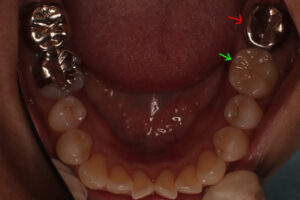

仮歯との違い と セラミックと金属の見た目

口腔内写真で明らかに違いが判るのは

保険で銀歯→ 自費で白い歯→

レントゲンでは神経の詰め物の状態の違い→